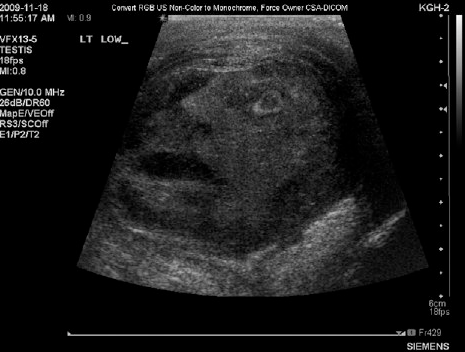

Publicado pela Sociedade Internacional de Urologia, a imagem de um rosto humano apareceu no ultrassom de um homem de 45 anos de idade que tem câncer nos testículos.

A imagem é tão nítida que é possível ver o que parece o desenho de um rosto com boca, nariz, olhos e até o contorno do da cabeça e as linhas da testa.

"Os médicos residentes e a equipe do hospital ficaram impressionados ao ver as feições de um homem na imagem", menciona a publicação.